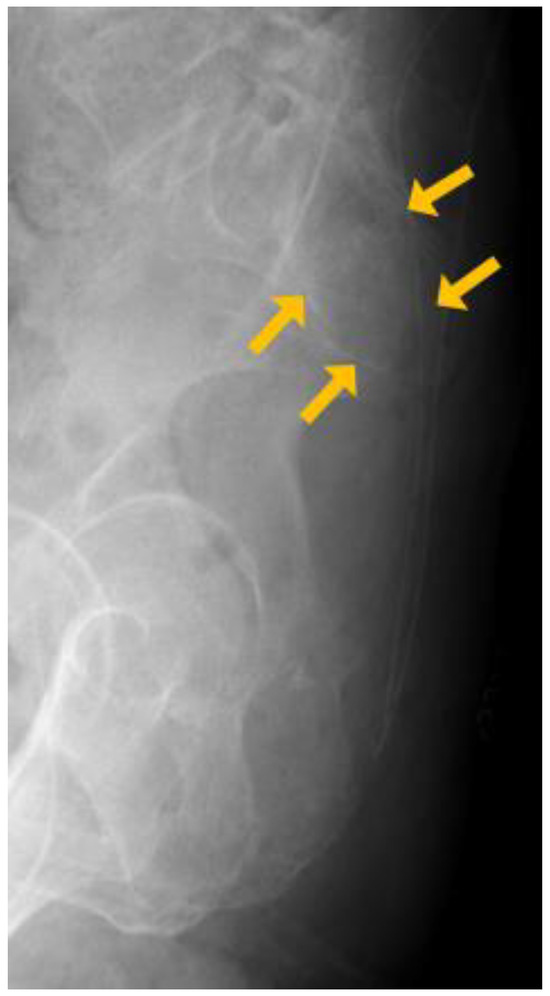

2. Case Report